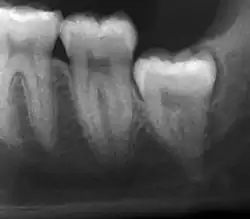

Impacted wisdom teeth are classified by their direction of impaction, their depth compared to the biting surface of adjacent teeth and the amount of the tooth's crown that extends through gum tissue or bone. Impacted wisdom teeth can also be classified by the presence or absence of symptoms and disease. Screening for the presence of wisdom teeth often begins in late adolescence when a partially developed tooth may become impacted. Screening commonly includes a clinical examination as well as x-rays such as panoramic radiographs.

The diagnosis of impaction can be made clinically if enough of the wisdom tooth is visible to determine its angulation, depth, and if the patient is old enough that further eruption or uprighting is unlikely. Wisdom teeth continue to move to the age of 25 years old due to eruption, and then continue some later movement owing to periodontal disease.[18]

If the tooth cannot be assessed with clinical exam alone, the diagnosis is made using either a panoramic radiograph or cone-beam CT. Where unerupted wisdom teeth still have eruption potential several predictors are used to determine the chance of the teeth becoming impacted. The ratio of space between the tooth crown length and the amount of space available, the angle of the teeth compared to the other teeth are the two most commonly used predictors, with the space ratio being the most accurate. Despite the capacity for movement into early adulthood, the likelihood that the tooth will become impacted can be predicted when the ratio of space available to the length of the crown of the tooth is under 1.[5]: 141